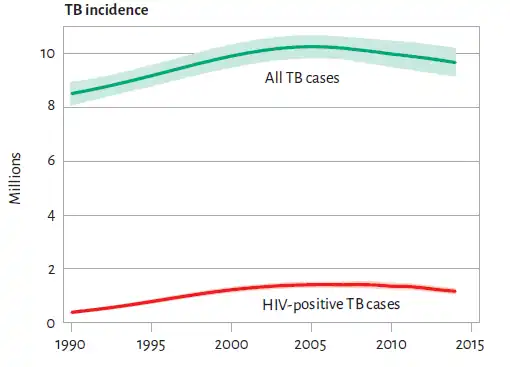

En 2023, après la pandémie de Covid-19, elle arrive en seconde place des causes de mortalité d'origine infectieuse à l’échelle mondiale, devant le sida[1]. L'Organisation mondiale de la santé (OMS) rapporte à travers son rapport annuel consacré à la tuberculose et sorti en 2015 que 1,5 million de personnes sont mortes de la tuberculose l’année précédente[2]. Parmi les nouveaux cas de tuberculose enregistrés en 2019, 87 % sont survenus dans les trente pays présentant la plus forte charge de la maladie. Deux tiers des cas sont concentrés dans huit pays, avec l’Inde en tête, suivie de l’Indonésie, de la Chine, des Philippines, du Pakistan, du Nigéria, du Bangladesh et de l’Afrique du Sud[3].

Le rapport 2015 de l’OMS rapporte également que la mortalité a baissé de 47 % depuis 1990 grâce en grande partie au développement des traitements ainsi que les modalités de dépistage et de prévention[2]. Cela représente un bon indicateur du progrès réalisé par les systèmes de soins, diagnostiques et thérapeutiques.

Le nombre annuel de nouveaux cas dans le monde, incluant les cas de rechute, était en 2006 d'environ 5,4 millions[29]. Il était en 2018 estimé à dix millions par l'OMS[30]. Environ 58 % des nouveaux cas se trouvent dans la région sud-est de l’Asie et les régions du Pacifique ouest. L'OMS estime par ailleurs qu'environ un quart de la population mondiale est porteuse d’une tuberculose latente, c’est-à-dire est porteuse de la bactérie sans toutefois développer de symptômes et sans être contagieuse. L'organisme estime entre 5 et 15 % le risque pour les porteurs sains de développer la maladie à un moment de leur existence[30].

La prévalence de la tuberculose en 2015 a chuté de 42 % depuis 1990. Elle varie d'un pays à un autre en fonction de plusieurs facteurs dont le niveau socio-économique ; le rapport annuel de l'OMS nous apprend que les pays en développement sont les plus touchés (95 % des cas) et en particulier la région de l’Asie du Sud-Est, avec 44 % des nouveaux cas et l'Afrique (28 % des nouveaux cas mondiaux en 2018). La tuberculose est une cause majeure de mortalité chez les personnes infectées par le VIH. Elle serait responsable de 13 % environ des décès par sida dans le monde[31].

Environ 1,5 million de personnes sont mortes de la tuberculose en 2018, dont une personne sur six était porteuse du VIH.

La tuberculose, sans bénéficier de programmes de prévention et de cure aussi importants, tue ainsi à peu près deux fois plus[32] que le sida, soit environ 4 000 personnes par jour[33].

Paradoxalement cette augmentation du nombre de morts, rapportée à l'explosion démographique mondiale, représente un progrès dans la prévention. Par rapport à 1990, c'est-à-dire sur une période plus longue, la baisse est en effet de 47 %[33]. Autrement dit, une politique de santé efficace montre au terme de quinze années ses limites face à un certain nombre de freins à la prévention. Face aux formes résistantes et multirésistantes de la maladie, la bataille s'achemine en 2015 vers une défaite[33]. Il manque au programme mondial de recherche coopérative les deux tiers de son budget annuel, lequel reste limité à 700 millions de dollars, alors que la dépense mondiale totale consacrée à la prévention, assumée principalement par les États, atteint presque 6 milliards d'euros[33].

En 2014, on estime à 190 000 le nombre de morts par tuberculose résistante[33]. Ils ont été recensés dans 105 des 205 pays transmettant leurs informations à l'OMS[33].